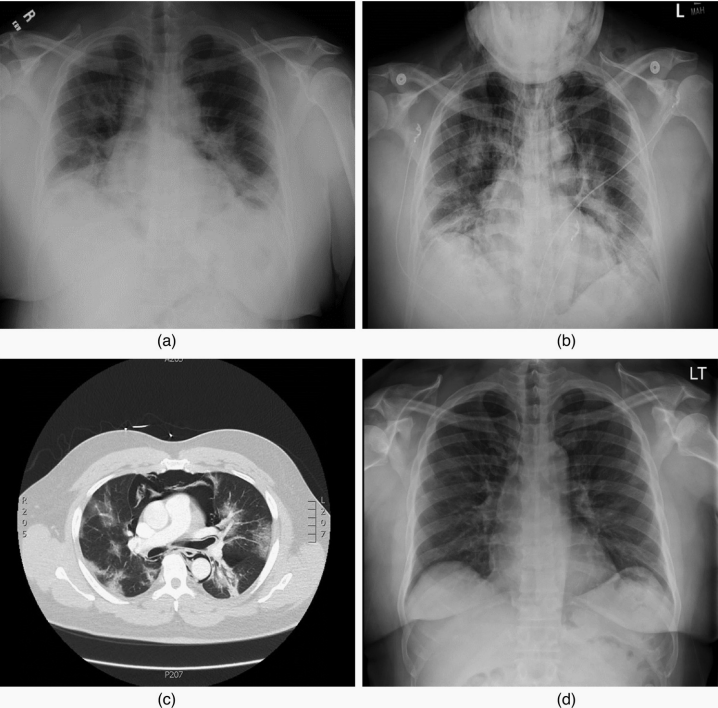

自发性纵隔气肿--男性,17岁,因逐渐出现胸部中央非劳累性憋闷而前来

图片尺寸1280x917